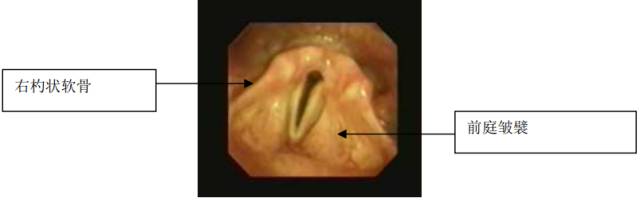

12以下图中会厌所显示,哪个是官方和公认的名字:

A. Ω或小儿型会厌

B. 马蹄形会厌

C. U型会厌

D. 普通型会厌

12D

这是一个正常的会厌。在成人男性,喉是5 - 7厘米长和正对第4、5、6颈椎。女性的会相对短和小。环状软骨的下缘是喉部最低的部分。环状软骨的是儿童气道最狭窄的部分(而声门开口或声门裂是成人上气道最狭窄的部分)。

双侧杓状软骨呈金字塔型与环状软骨上缘相连接。在他们的上方是小角软骨。corniculate软骨。真声带,也被称为声韧带,附在杓状软骨的后方,而假声带,也被称为前庭韧带,附在杓状软骨更高的顶壁上。 会厌软骨是一个单一的软骨位于舌根的后方。会厌软骨是通过1个舌会厌正中襞和2个舌会厌外侧襞与舌头相连接。正中和外侧襞之间的凹陷被称为会厌窝。在儿童和在一些成年人,会厌延长和弯曲。这被称为婴儿会厌、细长会厌或欧米茄会厌。